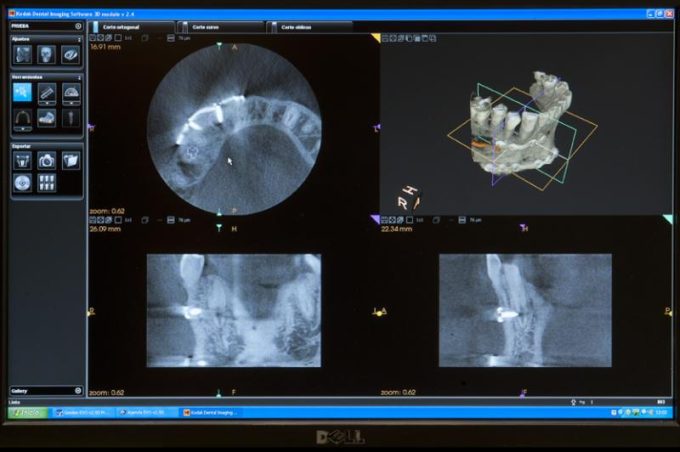

– El màxim nivell en el diagnòstic i tractament en els problemes odontològics i de salut bucodental.

– Fiabilitat científica en les proves i el tractament que li recomanem.